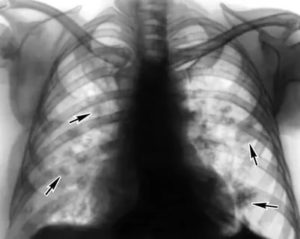

- рентгенографии, на которой можно обнаружить затемнение лёгочных полей различного диаметра, изменение кровеносных сосудов (лёгочного рисунка), уменьшение органа в размерах и смещение тени средостения в сторону поражения;

Для подтверждения диагноза «пневмосклероз» в большинстве случаев хватает проведения одной лишь рентгенографии лёгких.